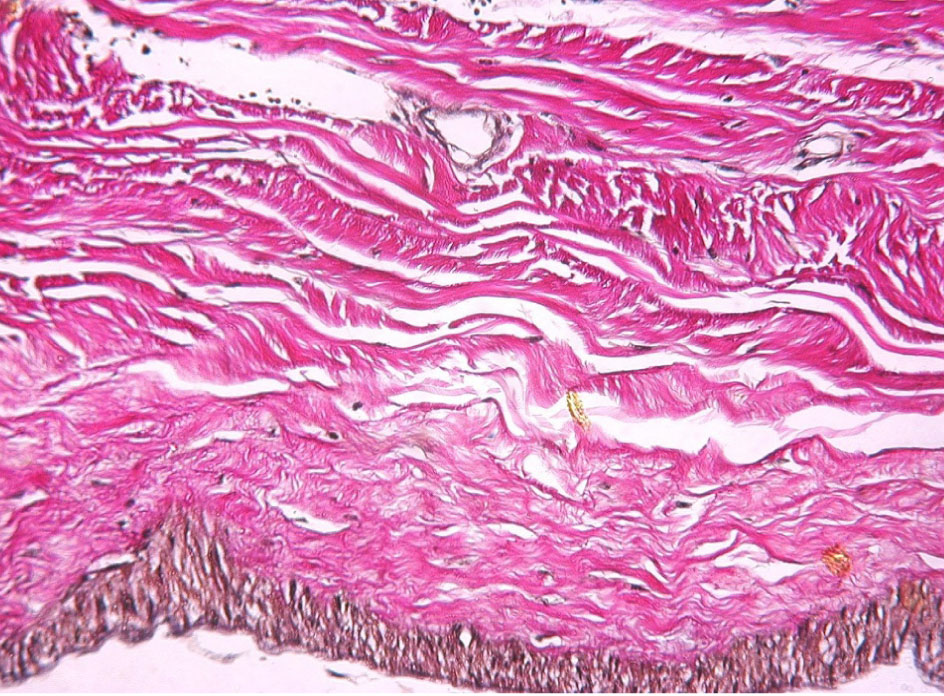

Рис. 3. Фрагмент ТМО мужчины 30 лет. Окраска по Ван Гизону. Увеличение ×80

Каждый слой имеет определенную гистологическую специфику, которая делает его по своему уникальным. Самый наружный – это периостальный слой, прикрепленный к внутренней части черепа с богатым микроциркуляторным руслом и хорошо выраженной иннервацией. Он состоит из удлиненных фибробластов, формирующих скопления, с большими межклеточными пространствами. Средний слой – менингеальный, представлен большим количеством фибробластов и небольшим составом коллагена, в сравнении с периостальным слоем. Самым внутренним слоем ТМО является слой погранично-клеточный, который иногда величают внутренним слоем клеток, мезотелиальным слоем или нейротелием [7, 12, 13, 14]. Этот слой гораздо тоньше, нежели периостальный и менингеальный, граничит с паутинной оболочкой. Он представлен несколькими слоями клеток, имеющих некоторые особенности эпителия (десмосомы и тонофиламенты), и практически лишен соединительнотканных волокон во внеклеточном пространстве. Поскольку погранично-клеточный слой хрупкий и легко разрывается, он, вероятно, играет ключевую роль при возникновении субдуральной гематомы [13, 14].